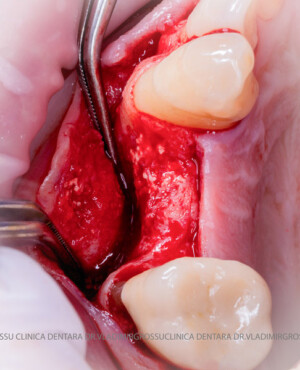

Aditia gingivală este o procedură chirurgicală ce corectează diverse probleme estetice și funcționale, cum ar fi recesiunea gingivală. În implantologia modernă, aditia de țesut moale este utilizată aproape în fiecare intervenție de inserție a implantului dentar pentru a asigura un aspect estetic natural și o bună integrare a implantului în cavitatea bucală.

Adiția osoasă are un rol crucial pentru poziționarea corectă și stabilă a implanturilor dentare. Clinica stomatologică Dr. Grossu din Chișinău promovează o abordare chirurgicală estetică și predictibilă, adaptată fiecărui caz în parte.